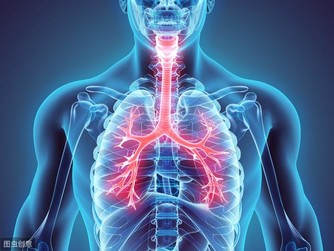

5、損害腎臟。

尿酸長期高,會導致肌酐高,這意味著腎臟可能出現問題,比如腎功能不全、甚至腎衰竭、尿毒症。尿酸結晶沉積導致腎小動脈和慢性間質炎症使腎損害加重。有研究顯示,尿酸可直接使腎小球入球小動脈發生微血管病變,導致慢性腎臟疾病。

高尿酸會增加腎功能降低風險21%,增加因慢性腎病死亡風險68%。